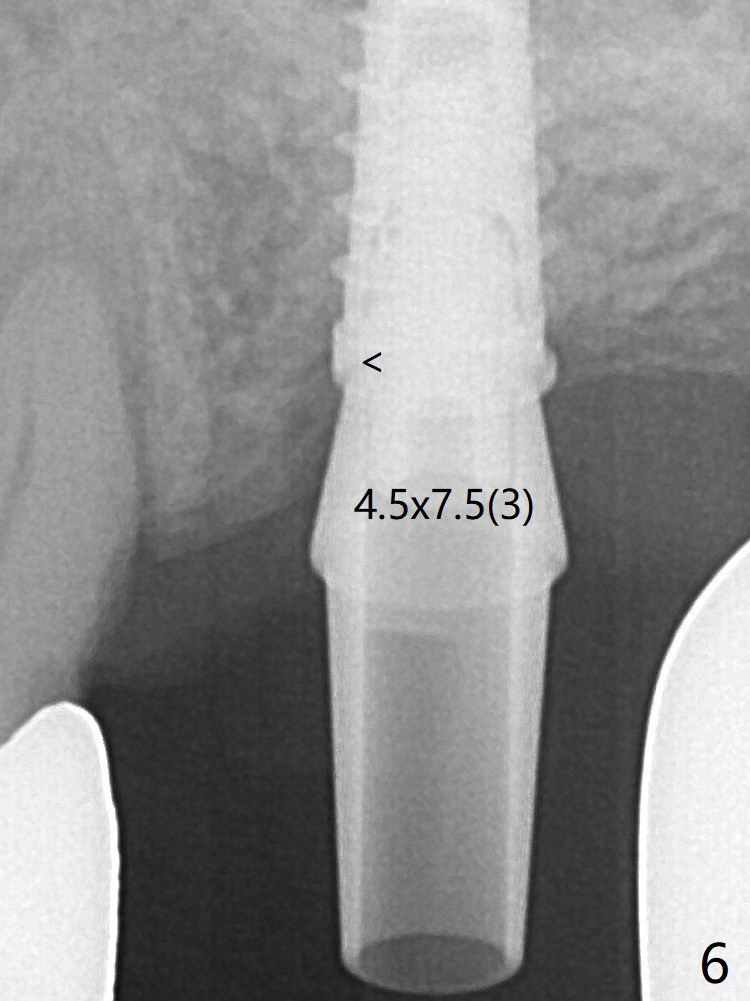

The crown/abutment at #14 is loose 1 year 10 months post cementation. After use of 5.5 mm profile drill, the crown/abutment is reseated, but the seating is incomplete (Fig.4 <) because of contact of the abutment with the mesial crest (*). A larger profile drill does not help (Fig.5). When a narrower abutment (4.5x7.5(3) mm) is torqued, it appears to be completely seated (Fig.6). After distal surface adjustment of the abutment, impression is re-taken. Depth Control Last Next Xin Wei, DDS, PhD, MS 1st edition 01/14/2020, last revision 01/14/2020